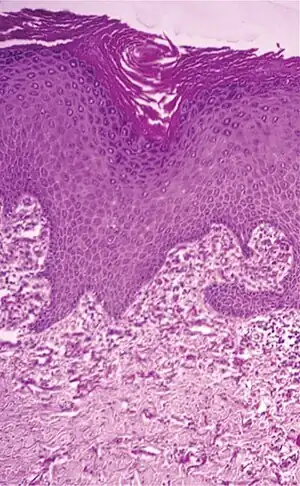

| Histopathology of perforating calcific elastosis: Clumping of short elastic fibers in the dermis.[2] | |

Perforating calcific elastosis is an acquired, localized cutaneous disorder, most frequently found in obese, multiparous, middle-aged women, characterized by lax, well-circumscribed, reticulated or cobble-stoned plaques occurring in the periumbilical region with keratotic surface papules.[3]